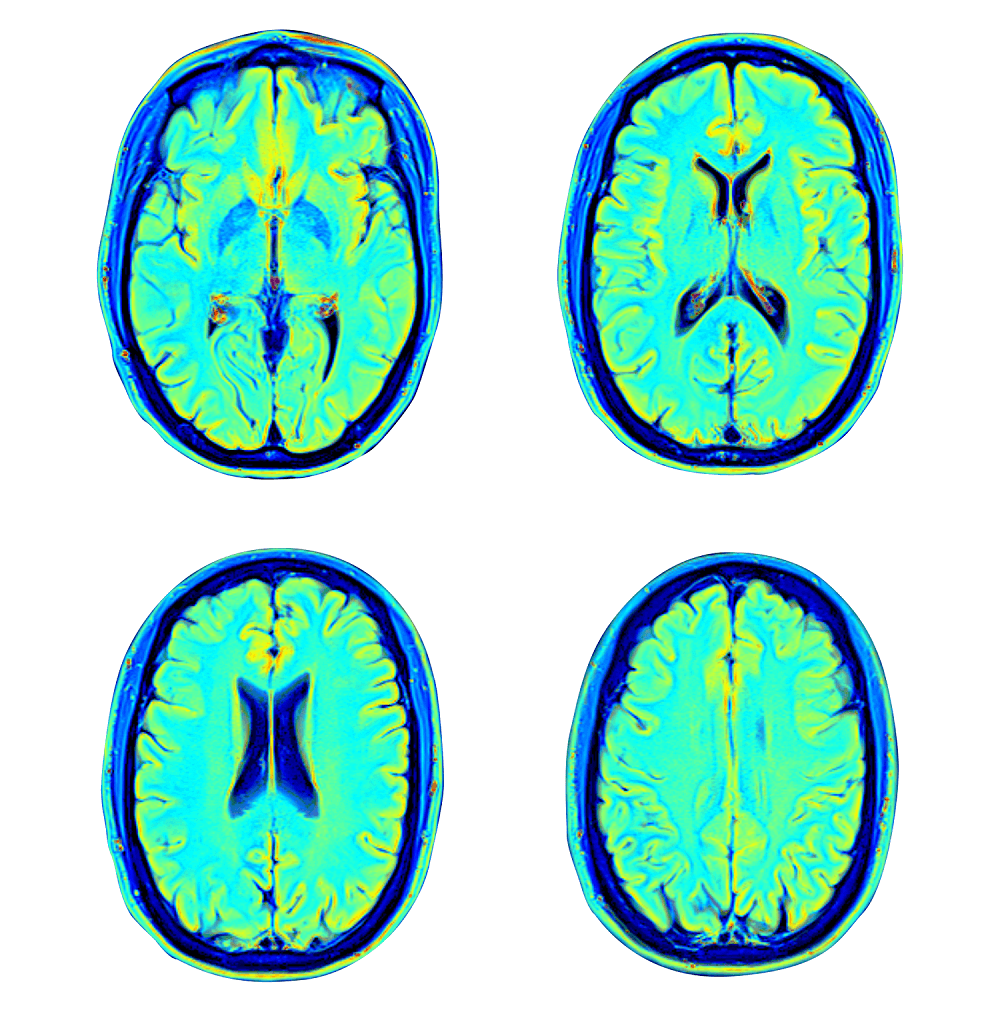

ونقوم كذلك بإجراء اختبارات للتمثيل الغذائي ووظائف الدماغ (التصوير بالرنين المغناطيسي لتروية الدماغ، واختبار تصوير البنية المجهرية بتقنية توتر الانتشار DTI)، ثم نحلل المؤشرات الحيوية المستجدة للشيخوخة في الدم، مثل طول التيلوميرات. وسوف تستكمل أيضاً مجموعة من التقييمات المعرفية العصبية والفسيولوجية واختبارات التغذية، بالإضافة إلى التسلسل الكامل للجينوم. -